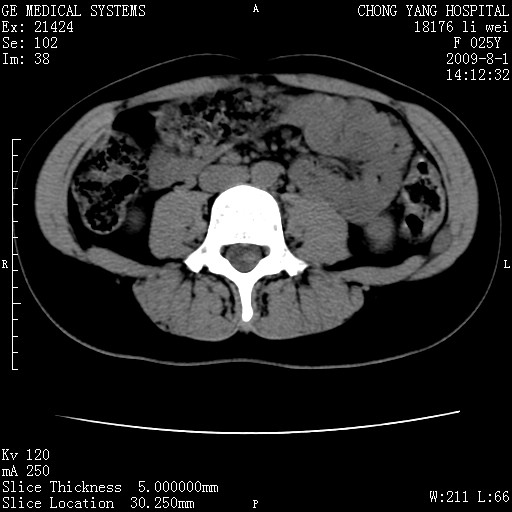

以下是引用pujunzhi在2009-8-1 20:23:00的发言:[br]胸椎旁及背部肌间良性病变,范围广,边界清,沿肌间生长,考虑淋巴管瘤、血管瘤,建议增强扫描。

以下是引用拾荒者在2009-12-30 21:45:00的发言:[br]ct21383:神经纤维瘤病( nf) [br] [br] 神经纤维瘤病。四肢都有,影响美观,四肢上的手术了。[br] [br] [br]谢谢!